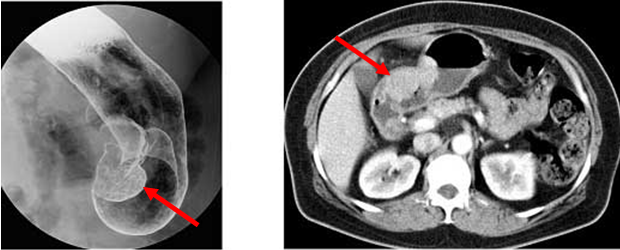

췌장은 소화 효소와 인슐린을 생산하는 장기로, 만약 이 장기에 문제가 생기면 심각한 건강 문제가 발생할 수 있습니다. 췌장염, 췌장암 등은 복부 CT를 통해 손쉽게 진단할 수 있으며, 췌장의 구조와 주변 조직 간의 상호작용을 명확히 확인할 수 있습니다. 특히 췌장암은 조기 발견이 매우 어렵지만, CT를 통해 미세한 종양까지 확인이 가능하므로 결과적으로 치료 효과를 극대화할 수 있습니다.

췌장염: 원인과 증상

췌장염은 췌장이 염증으로 인해 기능을 상실하는 질환으로, 주로 알코올 소비와 그에 따른 지방 간섭이 주요 원인으로 알려져 있습니다. 췌장염의 증상으로는 극심한 복통, 구역질 등이 있으며, 이러한 증상을 주의 깊게 살펴보는 것이 중요합니다. 복부 CT 검사는 즉각적인 진단을 통해 적절한 치료 계획을 세우도록 도와줍니다.